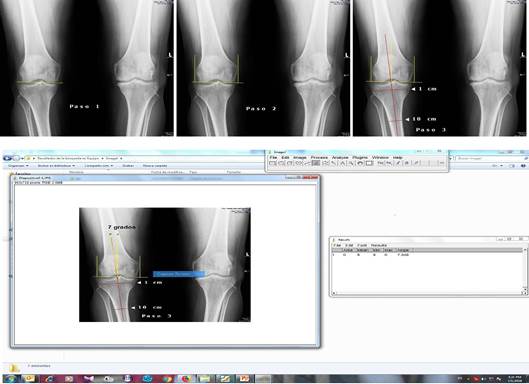

Esta medición se puede realizar tanto por vía digital como a mano en una radiografía simple de la rodilla. Una vez que se tiene la radiografía digital es llevada a formato de JPG, para continuar con los siguientes pasos (Figuras 2 y 3):

Paso 1: la imagen digital de la radiografía es llevada al power point, de allí se va a la sección de insertar y se traza una línea que une los dos límites más distales de ambos cóndilos femorales (medial y lateral).

Paso 2: se trazan dos líneas perpendiculares a la primera en los bordes de los cóndilos medial y lateral.

Paso 3: se traza una línea al tener en cuenta los puntos medios a 1 y 10 centímetros del borde articular de la meseta tibial, luego se dibuja otra línea en la intersección paralela a la de los cóndilos femorales, para establecer un ángulo cuyo valor es negativo en el varo.

Paso 4: se utiliza el software libre ImageJ, se abre la imagen a través de file-open, luego se marca la sección de ángulo, se realiza la medición al marcar analyse-measure.